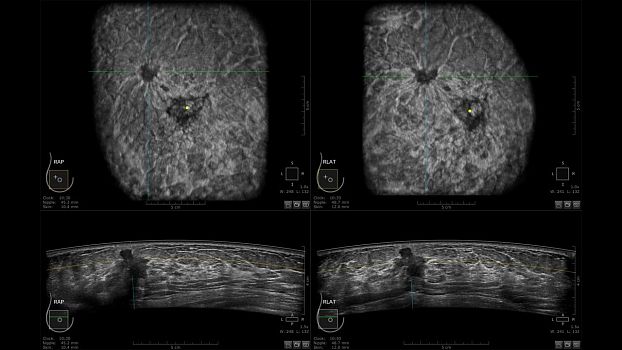

Клинические изображения

• Отображение объемных 3D ультразвуковых изображений, которые состоят из традиционных поперечных и воссозданных коронарных и сагиттальных проекций

• Возможность отображения полного 3D изображения

• Стандартизованная ориентация изображения:

• "толстый срез" в коронарной плоскости;

• поперечная;

• сагиттальная плоскость;

• радиальный и антирадиальный поворот изображения;